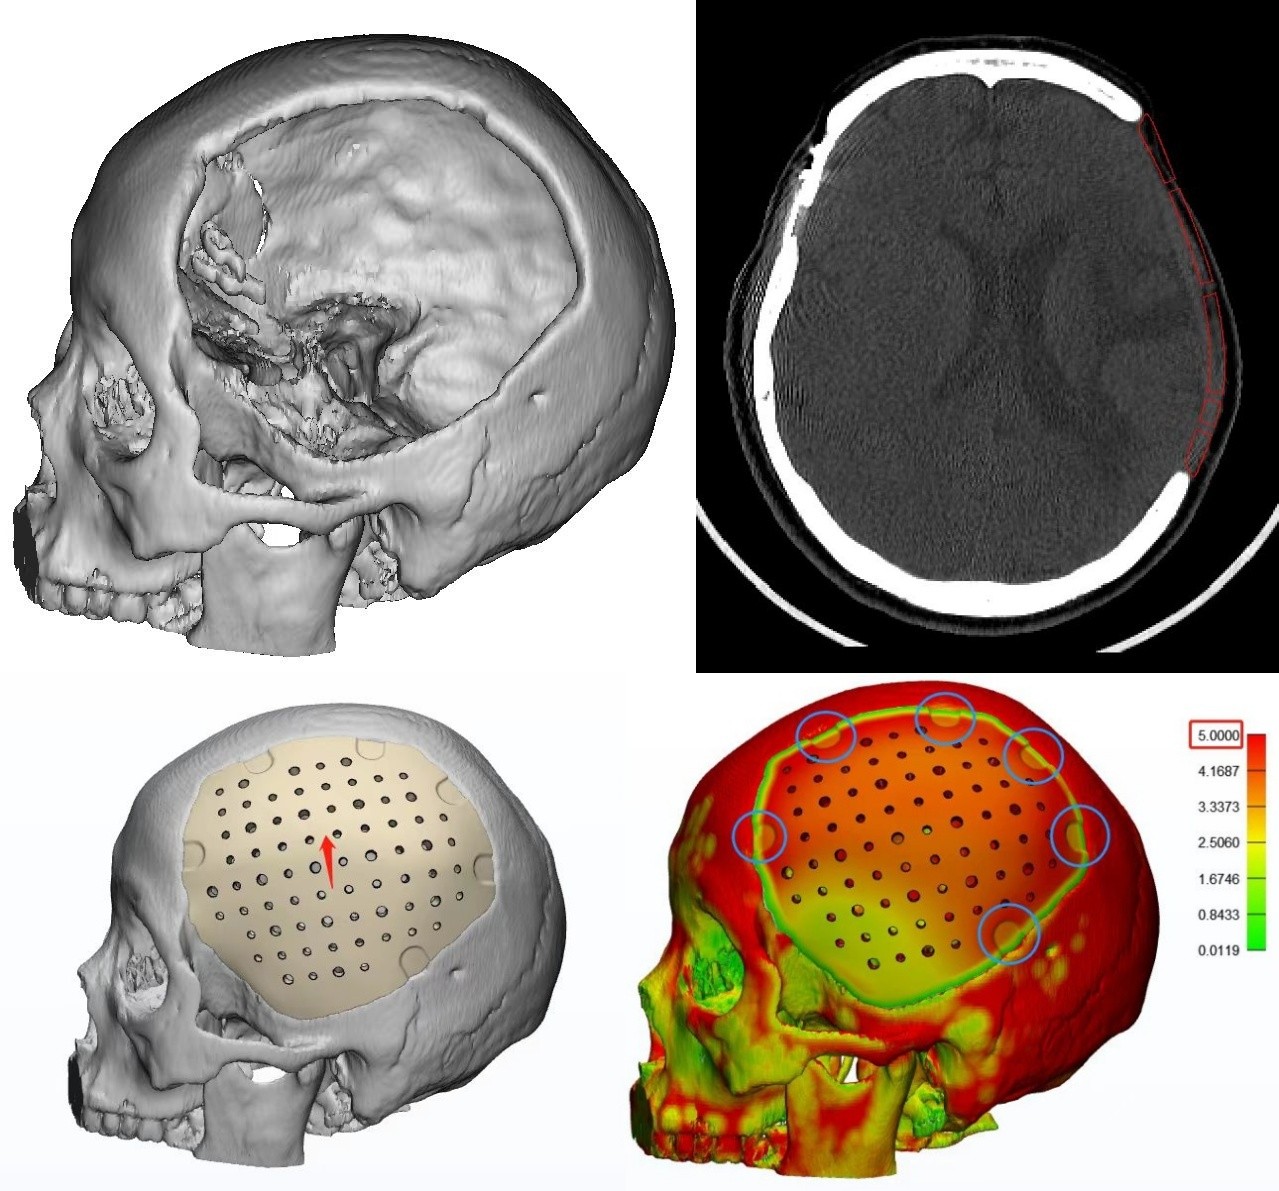

②術前設計PEEK材料假體弧度參考骨對稱設計,假體整體約0.5mm~0.6mm間隙設計,假體厚度約2.0mm-5.0mm,假體表面孔徑3/4mm穿插,假體共設計6個PEEK連接片凹槽用于固定。

①薄層頭顱CT數據.dcm格式上傳。

②連接片的位置及選擇——可選擇PEEK連接片或鈦連接片,PEEK板是否設置凹槽、高搭片。

③近顳底處PEEK材料的設計——解剖到位、骨窗緣充分暴露,一般顳部無需留空。

④假體厚度約2-5mm,假體間隙設計約0.5mm,假體孔徑為3mm、4mm穿插。